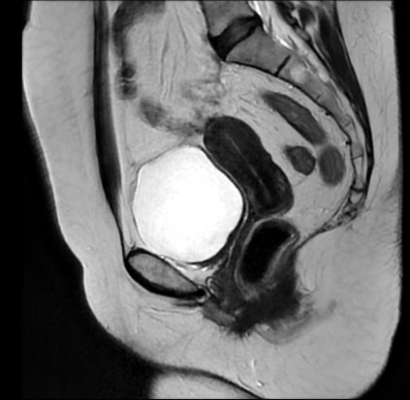

IRM du pelvis (prostate, rectum, canal anal) et IRM de l’appareil génital (utérus, ovaires)

L’IRM du pelvis et l'IRM de l'appareil génital permettent d’analyser les structures de la zone pelvienne et de distinguer les différents tissus mous qui composent les organes de cette région corporelle (vessie, urètre, utérus, vagin, ovaires, trompes utérines, vésicules séminales, prostate, rectum). Ces examens sont utiles pour confirmer un diagnostic comme : endométriose, kyste, lésions utérines ou ovariennes …